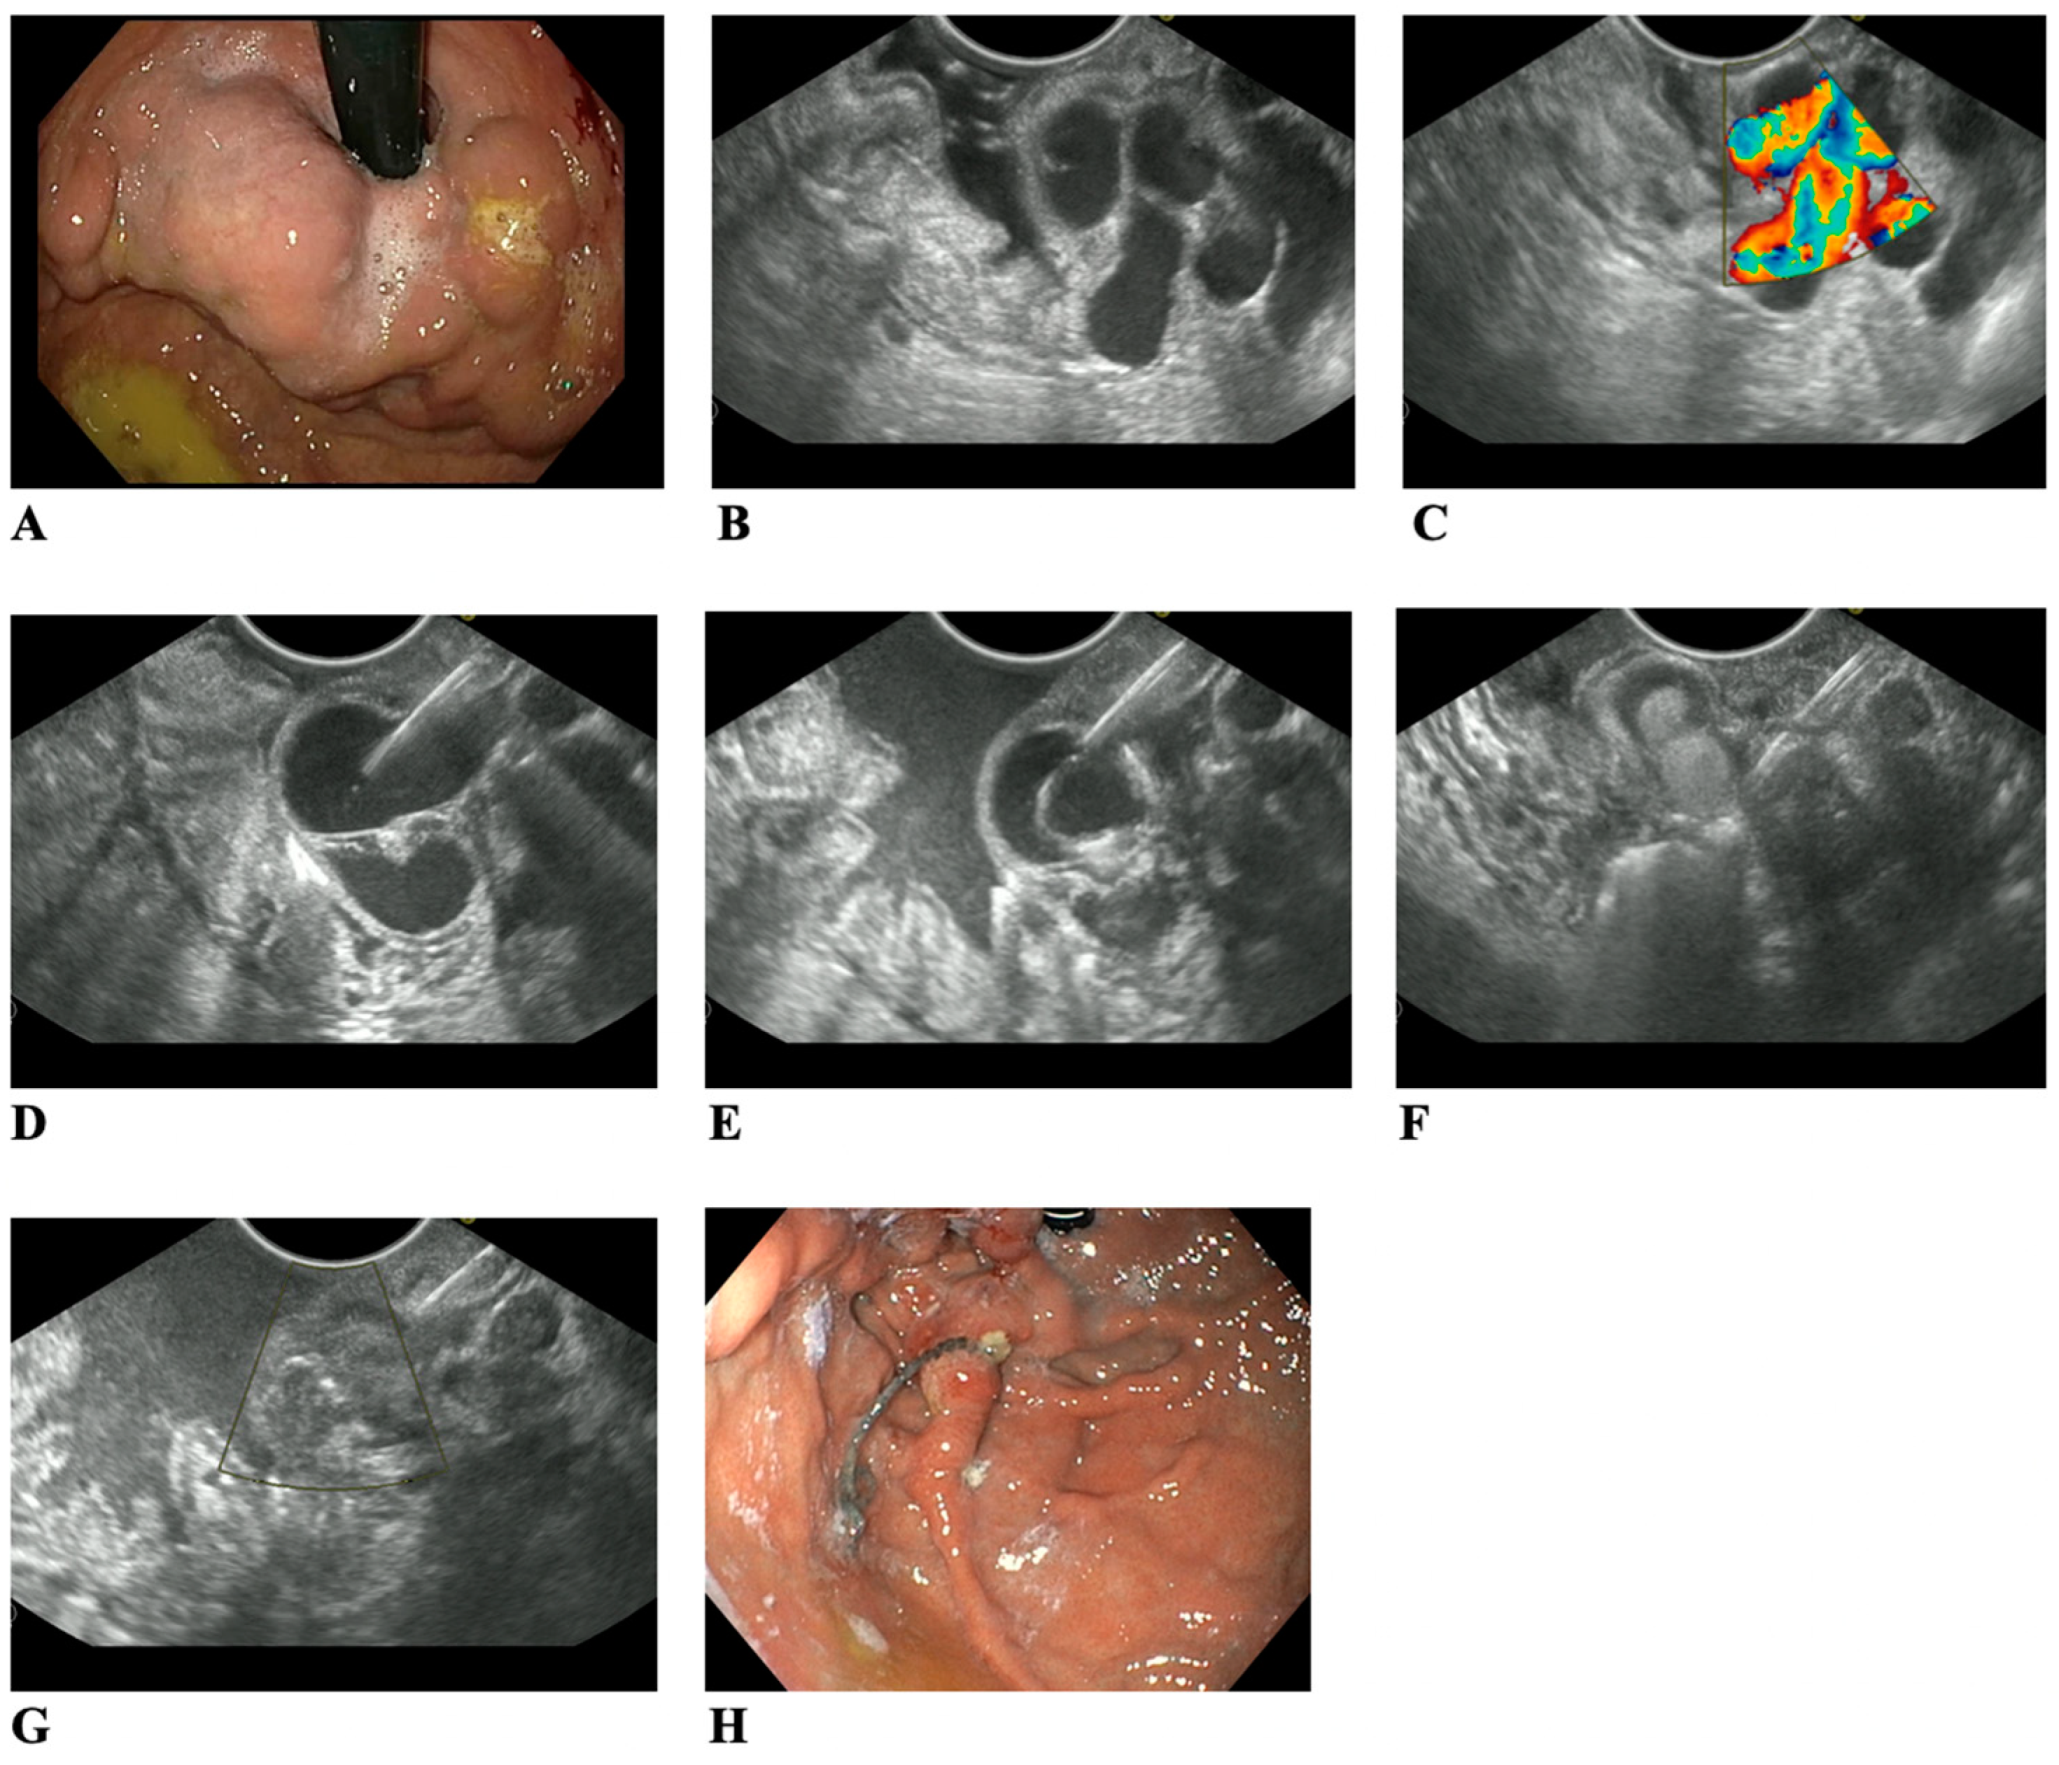

JCM Free FullText Endoscopic UltrasoundGuided Treatment of Banding After Endoscopy Variceal banding is a procedure that uses elastic bands to treat enlarged veins, or varices, in the esophagus. A physician places small rubber. Varices are swollen veins in your. Esophageal variceal bleeding is a medical emergency requiring immediate care, including an upper endoscopy to diagnose and ligate (band) the varices. It may also be called ligation. You had a procedure. Banding After Endoscopy.